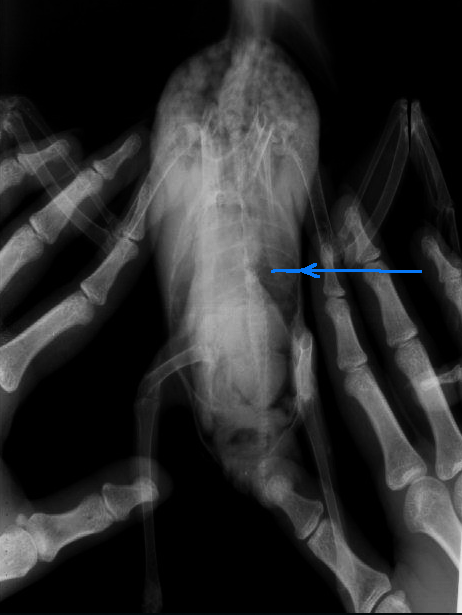

намочите перо по всей спине. И осмотрите позвоночник. Я отметила на рентгене где проблемное место. Хотя возможно это- всего лишь следствие наложения выворачивающейся из рук птицы...

NB- снято плохо, латеральаня проекция вообще не дает спину, зато хорошо видны все дистальные фаланги того кто птицу держал).